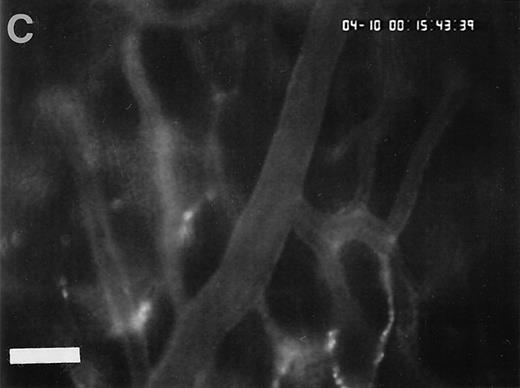

Accumulation of fibrinogen and platelets during I/R in vivo. Alexa 488-conjugated human fibrinogen (17 mg/kg) was administered intravenously 30 minutes before the induction of ischemia (left column). Rhodamin-labeled platelets were visualized in identical arterioles and venules using a different filter set (right column; see Materials and Methods). In wild-type animals (A,B), fibrinogen is bound unevenly to the vascular wall of arterioles and venules in the postischemic microvasculature. Areas with large amounts of fibrinogen (A, large arrow) can be seen besides regions without detectable fibrinogen deposition (A, small arrow). The accumulation of large amounts of fibrinogen colocalizes with platelet adhesion (B, arrowhead). In mice lacking ICAM-1 (C,D), the I/R-induced accumulation of fibrinogen and platelets is attenuated. Monitor magnification, 450×.

To assess fibrinogen deposition during I/R, the vascular distribution of fibrinogen was determined using immunohistology. In sham-operated animals small amounts of fibrinogen were detectable within the vessel lumen. Fibrinogen accumulation on the endothelial surface was not observed. In contrast, fibrinogen sequestration on the luminal surface of arterioles and venules was a prominent phenomenon after I/R. To investigate the time course of fibrinogen binding to the endothelial cell surface during I/R in vivo, fluorescent fibrinogen was administered intravenously before the induction of 1.5 hours of ischemia. In the physiologic state (baseline conditions), Alexa 488-conjugated fibrinogen was found homogeneously distributed in the plasma. No fibrinogen deposition was detectable in arterioles or venules (Fig 4). Similarly, during the ischemic period, no significant accumulation of fibrinogen on the endothelial surface was observed. In contrast, reperfusion dramatically enhanced fibrinogen binding to the endothelium in the postischemic microvasculature. Within 1 to 5 minutes after the onset of reperfusion, streaks of fluorescent fibrinogen were observed along the endothelial lining. After 10 minutes of reperfusion, the gaps between the streaks were partially filled with fibrinogen, resulting in a heterogenous fibrinogen coat on the endothelial cell surface of the majority of all vessels studied. In most instances, significant fibrinogen deposition at the arteriolar and venular endothelial surface coincided with the adhesion of platelets in these areas (Fig 4).

To determine the role of ICAM-1 as an endothelial fibrinogen receptor, the accumulation of Alexa 488-conjugated fibrinogen during I/R was investigated in mice deficient in ICAM-1. No fibrinogen binding was seen under control conditions or during ischemia. During reperfusion, a moderate increase in endothelial fibrinogen binding occurred in few arterioles and venules (Fig 4), while the majority of the vessels studied showed no significant fibrinogen accumulation, indicating that ICAM-1 is in fact involved in mediating the deposition of fibrinogen at the postischemic endothelium. To evaluate whether ICAM-1–dependent fibrinogen sequestration on the endothelial surface might mediate platelet-endothelial cell interactions during postischemic reperfusion, fluorescent wild-type platelets were infused into ICAM-1–deficient animals (Fig 1). Whereas the number of rolling platelets did not differ from wild-type mice (23 ± 5 and 36 ± 4 platelets/s/mm in arterioles and venules, respectively), platelet adhesion was significantly reduced in the absence of endothelial ICAM-1: 125 ± 42 and 71 ± 27 platelets were seen firmly attached per mm2 endothelial cell surface of arterioles and venules, respectively, indicating that ICAM-1 is in fact involved in platelet recruitment during postischemic reperfusion.